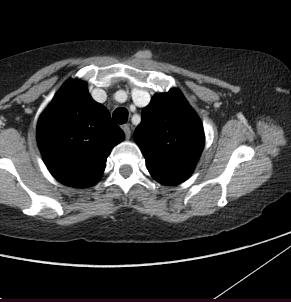

Rolul CT-ului în managementul cancerului rectal

Tomografia computerizată (CT) este una dintre primele investigații imagistice recomandate după confirmarea diagnosticului de cancer rectal. Aceasta poate oferi și unele informații despre invazia tumorală locală, dar rolul ei principal astăzi constă în evaluarea extensiei la distanță a bolii, fiind excelentă pentru identificarea metastazelor pulmonare și hepatice. CTul permite o evaluare rapidă și detaliată a cavității abdominale și toracice, având un rol cheie în stadializarea TNM (Tumor, Node, Metastasis) a cancerului.

aproximativ 10-20 de minute, în funcție de complexitatea cazului și de necesitatea explorării mai multor regiuni anatomice. În mod uzual, în cadrul stadializării inițiale sunt evaluate toracele, abdomenul si pelvisul. De menționat că investigația CT este una iradiantă pentru pacient, raportul risc-beneficiu fiind totuși net în favoarea efectuării acesteia la pacienții diagnosticați cu cancer rectal.

Examinarea CT poate fi combinată cu tomografia cu emisie de pozitroni (PET), formând o tehnică de imagistică hibridă cunoscută sub numele de PET-CT. Aceasta presupune injectarea unui radiotrasor, de obicei fluorodeoxiglucoză (FDG), care se acumulează în zonele cu activitate metabolică crescută, tipică celulelor tumorale. Imagistica PET evidențiază aceste regiuni metabolice active, în timp ce CT-ul suprapus oferă detalii anatomice precise. PET-CT este o tehnică avansată, rezervată unor cazuri selectate, deosebit de utilă în stadializare în privința leziunilor secundare sau recidivei tumorale.

Metastaze pulmonare. Examen CT multislice, fereastră pulmonară, plan axial.

Din colecția Centrului de Imagistică, UMFCV